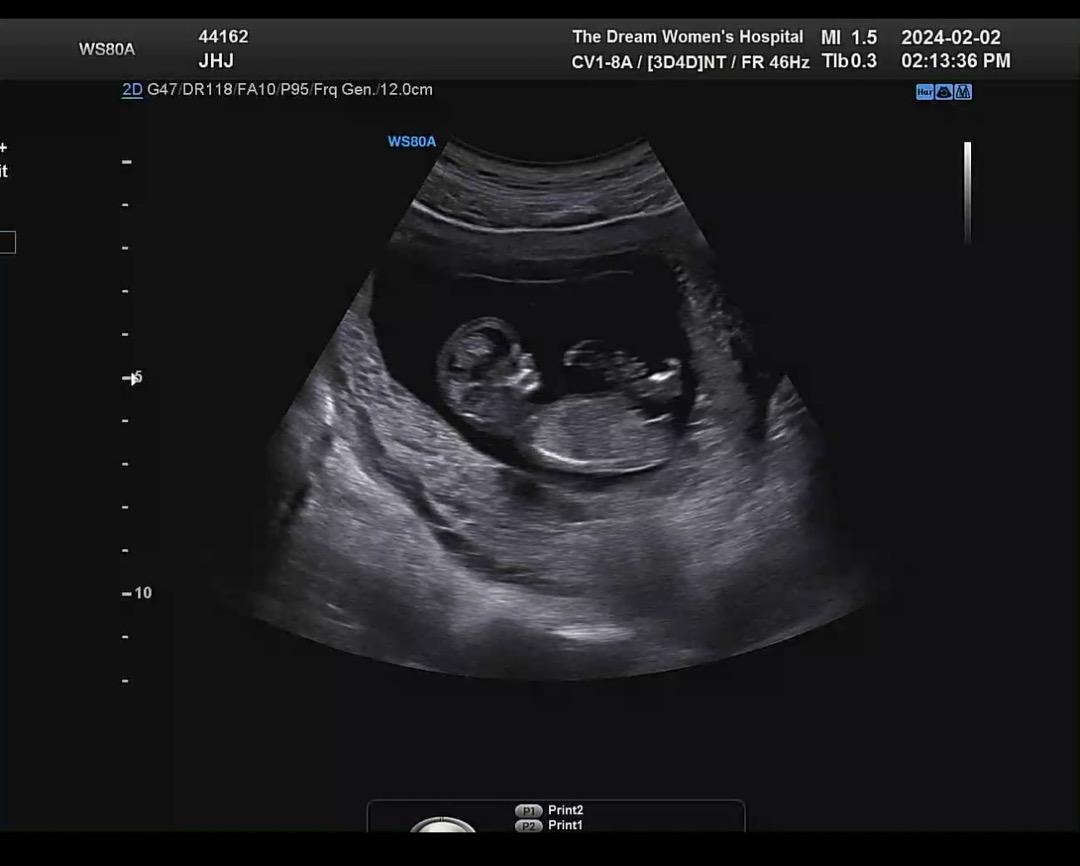

오늘 1차기형아 검사하고왓어요 ! 성별은 아직 모르는거겟져,,

목둘레 정상이고 주수보다 아이가 조금 크고,, 오늘 갓더니 아빠다리 하고있다가 누웟다가 팔다리 휘젓고 난리엿어요 ,,, ㅋㅋㅋ 각도법이 따로 잇다는데 봐도 모르겠는 1인 ,,, 남편쪽이 남자만 둘이라 남자아이일꺼같다는 어른들의 말 ,, 각도법은 도대체 어떻게 보는건가요 ㅠㅠ

제..초음파 꼬추 각도와 같네요..아들이십니다

앜ㅋㅋㅋㅋ그쵸 !! 입체 촘파도 탯줄옆에 꼬추같아보이는데 남편은 자꾸 아니라고 아니라고 그래서 넘 긴가민가하네요 ㅠㅠ 감사합니다!!!!!!!!